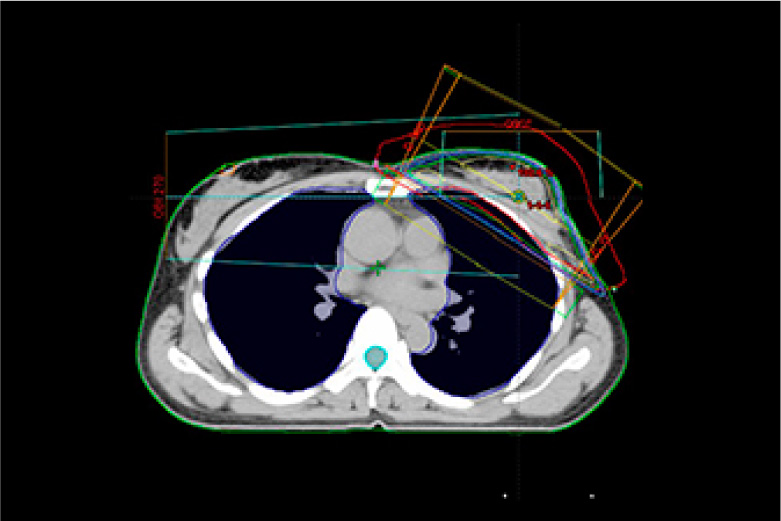

放射線治療とは身体できた病巣部に放射線を照射しがん等の病気を治す治療法です。

手術と比較し身体への負担が少なく病巣部を安全かつ効果的に治療することができます。

当院で使用する放射線は高エネルギーX線及び電子線で直線加速器(リニアック)を用いて人工的に放射線を作るため目的に応じた線質、強さ、量に調整することができます。

実際の治療ではまず治療開始前にCT撮影を行い、照射する場所、範囲、放射線の量等を専用の機器を用いて決定します。(下図参照)これをもとに治療時には装置に搭載されたX線撮影装置、CT装置にて画像を撮影し3次元的に位置照合を行い計画された方向より照射します。

治療装置は360度どの方向からでも照射可能で病巣を多方向から正確に照射することで治療効果の向上、病巣周囲の正常組織の線量を減らすことができます。

バリアン True Beam